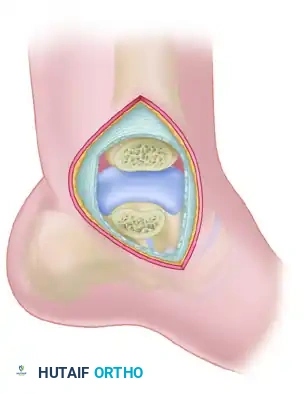

The Hawkins Sign

Between 6 and 8 weeks post-injury, an AP radiograph of the ankle should be scrutinized for the Hawkins sign.

* Positive Hawkins Sign: A thin line of subchondral radiolucency (atrophy) along the dome of the talus. This indicates that the bone is vascularized enough to undergo disuse osteopenia. It is a highly sensitive indicator that AVN will not occur.

* Negative Hawkins Sign: If the bone remains dense and sclerotic relative to the surrounding osteopenic bone, osteonecrosis is likely present.